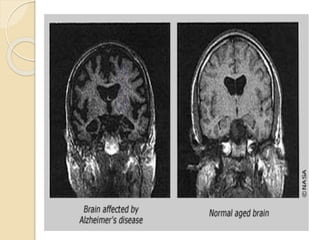

 The pathologic hallmarks of the disease in

the brain include neurofibrillary tangles and

neuritic plaques made up of various

proteins, which result in a shortage of the

neurotransmitter acetylcholine.

 These are primarily located in brain regions

involved in learning, memory, and emotional

behaviours such as the cerebral cortex,

hippocampus, basal forebrain, and

amygdala.